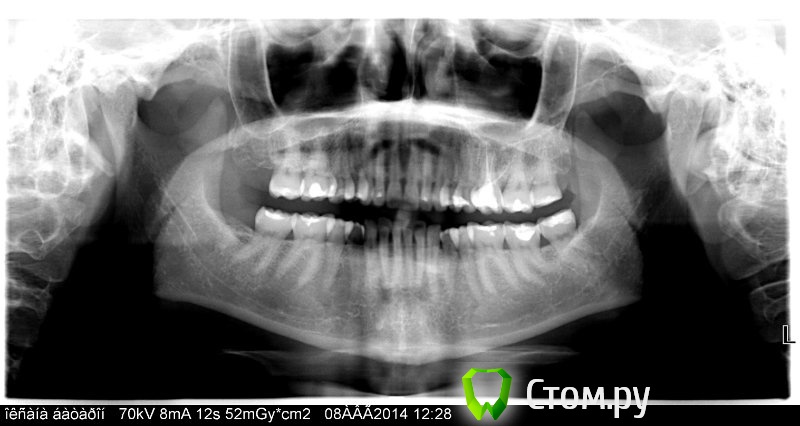

oksanab Опубликовано 2 октября, 2014 Поделиться Опубликовано 2 октября, 2014 (изменено) Консультировалась уже с 4-мя ортопедами, при чем кандидатами мед. наук, и они как-то расходятся во мнении. История такая: 12 лет назад зуб депульпировали, лет через 6 я стала ощущать дискомфорт, и на снимке было воспаление. (снимок 1). А теперь 1,5 месяца назад воспалились немного десна и через какое-то время появился флюс. Вскрыть десну я побоялась и пропила антибиотики. Флюс сошел, но десна еще оставалась припухлой слегка. Я после этого, то есть после антибиотиков, пришла к ортопеду, он начал лечить каналы 26-го зуба, и дискомфорт в десне на половину уменьшился, то есть явно стало получше. В этом зубе так же был обнаружен кариес, но врач сказал, что после лечения каналов удалит кариес, может за стенки боялся). Но во время лечения, когда стояла лечебная паста, на отдыхе зуб сломался об косточку оливки(стояла временная пломба с пастой лечебной). Ортопед через 20 дней убрал лекарство и запломбировал каналы эндометазоном(про гутаперч ничего в выписке не пишет, только это). Когда пломбировал, просил у медсестры что-то 40-е или хотя бы 38-е, у них не оказалось(может штифты...). Уж не знаю чем они там обошлись, но меня такая клиника напрягла. Врач поставил временную пломбу, удалил кстати, отломавшийся кусочек зуба, и сказал приходить через 3 дня, чтобы удалить кариес в этом зубе и смотреть его устойчивость, чтобы определиться с коронкой или вкладкой. Поскольку в этой клинике вечно чего то нет, я перешла в другую. Пришла к кандидату мед. н аук с 25 летним стажем. Он заявил, что скорее всего нужна резекция корня зуба, и отправил меня в институт научно-исследовательский(ЦНИИС и ЧЛХ). Так я попала к следующему к.м.н.- ортопеду Мурадову. Этот радостно сообщил ,что все замечательно, резекции не надо. Но он пропустил кстати перфорацию корня у дистально щечного канала , как и первый к.м.н., он тоже пропустил ее,( его только воспаление у десны обеспокоило, поэтому отправил в институт на консультацию в институт.) А вот уже в институте второго ортопеда -к.м.н. -Мурадова, ничего по десне не обеспокоило, сказал будем ставить коронку. Пока ждала 2 недели очередь , так уж получилось, что я сходила еще к одному ортопеду, чтобы заменил временную пломбу. Он посмотрел снимок, и он первый из врачей, кто вообще заявил, что есть перфорация корня и зуб надо удалять! Однако, я вернулась все таки пошла на лечение к Мурадову ,который радостно брался за этот 26 зуб. И когда я пришла на лечение через 2 недели по его огромной записи, тут вдруг выяснилось... Он вскрыл зуб, сказал что-то про запах, сразу его запаял и заявил, что паста мягкая, надо перепломбировать. Паста - эндометазон. Я попросила повнимательнее посмотреть на снимок, и посмотреть есть ли там перфорация. Тут наконец-то перфорацию заметил и он, хотя видел снимок и две недели назад, и сегодня перед началом лечения. В итоге мне заявил, что, ну пусть терапевт разберется есть там перфорация или нет, потому что на обзорном снимке видно, что угол у зуба другой. Прилагаю три снимка(зуб до лечения, и общий снимок до лечения, и зуб после лечения и пломбировки каналов эндометазоном и уже со сколом зуба). Так вот он все-таки не совсем понял, есть ли перфорация канала. Отправилась я тогда к зам. главного врача этого института ,она оказалась тоже к.м.н. и именно ортопед. Может она конечно хотела прикрыть Мурадова, не знаю, но сказала, что хотя она не очень знает эндометазон, но тоже считает, что надо сделать перепломбировку. На мой вопрос почему врачи, да еще и к.м.н. не замечают перфорацию, ответила, что это конечно не хорошо, но и ей лично кажется, что все-таки перфорация есть. Однако ей было сложно рассмотреть мои снимки на айфоне, то есть я показывала снимки с своего телефона. Поэтому она порекомендовала мне записаться к их терапевту, чтобы внимательнее просмотрел все, может снимок сделал еще один, и чтобы перепломбировали канал методом латеральной конденсации, и пролечили перфорацию. И кстати говоря ,не рекомендовала не резекцию корня зуба, ни его удаление. По факту что у меня получается. Первый к.м.н. - за резекцию корня. Остальные три против резекции. Пятый ортопед вообще за удаление. И вот через 4-5 дней из-за очередей попаду к их терапевту какому-то толковому, тоже будет мозговать, есть ли перфорация, и чего делать то. Народ спасите. ЁПРСТ, я с этим зубом уже полтора месяца хожу, а они только трепятся, а за лечение никто еще не взялся. Только мне все истории разные рассказывают. Я уже готова и удалить его, хотя очень импланта боюсь. И готова рискнуть, поставить коронку, а если чего будет, ну резекцию тогда. Но тот врач, который сказал, что зуб надо удалять, сказал, что и резекция всего лишь временно поможет и толку в ней не будет. Блин, блин, блин... Как я простой человек могу в этом разобраться. И вообще , я больше месяца только на одну сторону жую ,это же тоже наверно не очень хорошо. Перелеченный недавно зуб на втором снимке со сколом зуба. Изменено 2 октября, 2014 пользователем oksanab Ссылка на комментарий